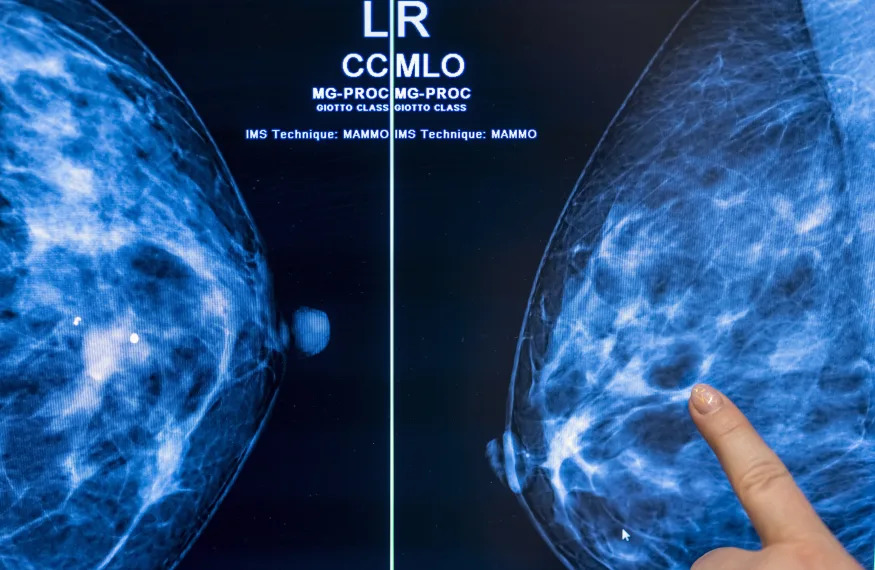

La detección del cáncer asistida por IA podría reducir la carga de trabajo de...

Un estudio recientemente publicado en el Oncología de lancetadiarioha descubierto que el uso de IA en la detección del cáncer con mamografías puede reducir...